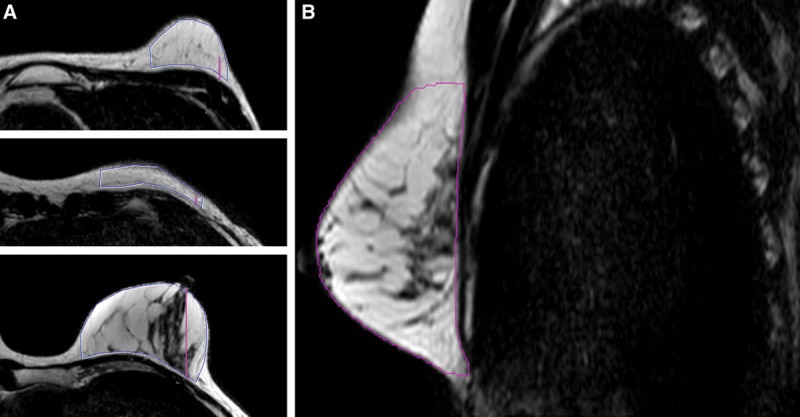

(图. 乳房的MRI图像。A,对于此目标区域,使用乳房凸面的轮廓来定义上下边界。B,在上下边界之间的轴向图像上绘制了目标区域。)